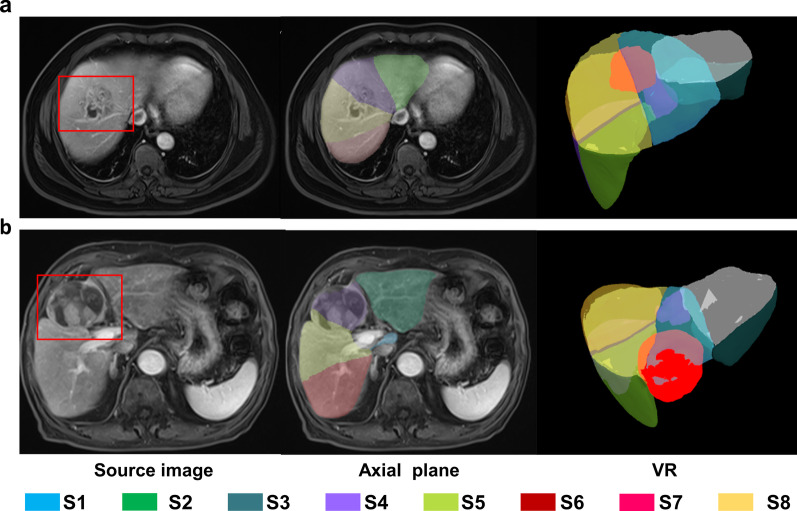

The accuracy of segmentation was assessed indirectly based on the localization of lesions in the liver. The steps were as follows: first, cases with uncountable lesions or no lesions were excluded. Then, for each of the remaining cases, all the focal abnormal findings (larger than 5 mm) that could be seen in PVP were identified. If a liver had more than five lesions, only the five largest lesions were selected. Finally, for each eligible lesion, the specific liver segment that it resides (by only referring to the automated segmentation results) was recorded and judged by radiologists. Detection, screening, and localization judgment of lesions were performed by two radiologists (X.H. and Y.D.W.) in consensus. One radiologist (Y.Z.H.) arbitrated in case of disagreement. Fig. 3 illustrates the indirect evaluation with two examples.

Fig. 3.

Examples of indirect evaluation. a A liver abscess that resided in S4 and S8 was assigned to the correct segments by AI. b Shows a large tumor, located in S4 with slight pushing of the margin of S8. However, if we only refer to the AI segmentation result, it will be assigned to S4 and 8. The red boxes in the source image and bright red volumes in VR images indicate the lesions. AI, artificial intelligence; S, segment; VR, volume rendering.

Indirect evaluation

After excluding 46 cases with no or uncountable lesions, a total of 106 lesions from 54 patients were used to evaluate the accuracy of AI segmentation. The maximal diameters of all lesions ranged from 0.6 to 6.0 cm (mean +/− SD, 1.6 cm +/− 0.8 cm) on MRI. According to the results, 93.4% (99/106) of the lesions were assigned to the segments where they were actually located. Moreover, the proposed method not only accurately located small lesions in a single segment but was also effective for massive lesions across segments. Seven of 106 lesions in total failed to be accurately located, of which two were due to the severe segmentation errors. Of the other errors, four lesions were on the boundary between two segments, and one lesion was on the edge of the liver and was not included in the segmentation.

Previously, the evaluation of liver segment segmentation was mostly performed by visual inspection [7] and volumetric validation [16–18, 20, 21], or a combination of both [10, 19]. It is a major challenge because it imposes to have actual segment specimens. Several recent studies have adopted new approaches, including quantitative assessment, qualitative assessment, and indirect assessment [4, 5, 8, 9]. However, they all have a small sample size problem. In this study, we made a thorough evaluation of the model by using three different methods. Quantitative evaluation provides exact results and allows comparison between different studies. A common metric used for this purpose is DSC. To date, the accuracy of liver segment segmentation produced by prior methods does not exceed a DSC of 88.2% [5]. In this work, our model yielded a mean DSC of 90.2%. Good results were also obtained in HD, MSD and RV, metrics that have not yet been reported in similar research but have been widely used for segmentation evaluation. As a part of our experiment, the model was applied to real clinical scenarios for evaluation. As expected, our model generated good segmentation images in most cases, covering a wide range of liver appearances from normal to abnormal. It is worth mentioning that some cases with advanced liver cirrhosis or multiple liver metastases were also accurately segmented by our model and some of the large across-segment tumors did not affect the detection of boundary lines. Poor segmentation occurred mainly in cases with severe vascular problems, including abnormal vascular routes or vessels that were badly invaded by tumors. This problem may be solved by collecting this kind of case and retraining the model. Additionally, our approach has shown promising results in assisting lesion localization. As shown, 93.4% of the lesions were localized in the right segments simply by referring to the segmentation results without using any medical experience. This is meaningful considering the important role of automated lesion localization for future liver computer-aided diagnosis systems. Further investigating the mislocalized lesions, we found that most of them were at the edge of segment and pushed the borderline between two adjacent segments (Fig.3b). They were often mistaken for a cross-segmental lesion according to automated segmentation results. Only a few mislocalizations were caused by the real severe segmentation errors of liver segments.